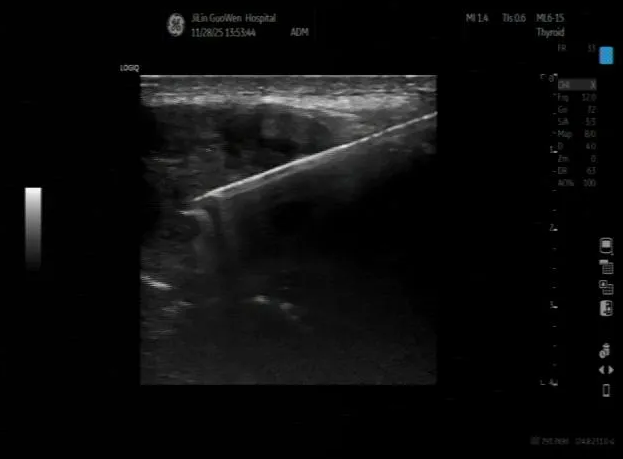

刘先生(化名)近期被右臀部肿块及下肢剧痛困扰,肿块持续增大,疼痛已严重影响行走,家人随即搀扶他前往我院就诊。超声检查显示,其右臀部探及大小约15.9*8.0*10.3cm的实性为主不均质混合回声肿块,深方与骨分界不清且骨皮质不光滑,实性部分可见血流信号,超声科医生敏锐判断“考虑恶性”。

为明确肿块性质,超声科为刘先生实施超声引导下肿物穿刺活检,病理结果显示为“转移性低分化癌”,结合免疫组化,考虑为肝脏来源的肝细胞肝癌(3级)。